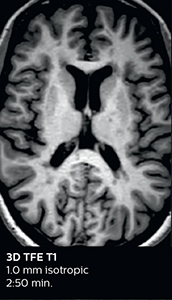

3D FLAIR (with Compressed SENSE)

3D FLAIR

1.0 x 1.0 x 1.0 mm*

2:50 min.